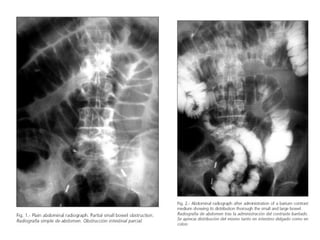

SIGNOS RADIOLÓGICOS EN LA

Obstrucción mecánica

simple

Gas en intestino

• Asas grandes arqueadas

en patrón de escalera

Menos del normal

• Niveles de líquido en

intestino Precisos

• Tumor Exudado

peritoneal Diafragma

Ninguno

• Un poco elevado;

movimiento libre

íleo adinámico

• Gas abundante difuso en

todo el intestino

• Aumentado, diseminado

en todo el colon

• Con frecuencia muy

grandes del principio al

fin

• Ninguno

• Existe cuando hay

peritonitis: de otra

manera no se presenta

Elevad >; movimiento

disminuido